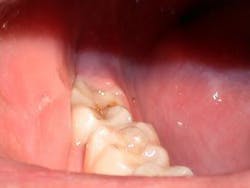

Often when a general dentist is restoring lower molars, an operculum can be found which can hinder his or her restorative endeavors (Fig. 1). The perfect tool for removing this operculum and assisting the dentist is the soft-tissue laser. The soft-tissue laser can remove the offending operculum atraumatically, often with little or no anesthesia and no postoperative discomfort or bleeding. Those who practice microdentistry with air abrasion or a hard-tissue laser can be particularly assisted by the durable hemostasis afforded by a soft-tissue laser. Those dentists who are familiar with hard-tissue lasers know that, although soft-tissue surgery is possible with the Erbium wavelengths, the hemostasis that is afforded can be negligible in all but the healthiest tissues. This is a fact that is supported by the physics of the wavelengths. The author, who is a lecturer for bioLitec is particularly excited by the excellent tissue effects, no charring and durable hemostasis, that are derived by the 980nm wavelength of the bioLitec SmilePro 980. This wavelength has the highest water absorption of all of the near-infrared wavelengths. Since tissue is comprised of nearly 60 to 80 percent water, water absorption is a valuable property in tissue-cutting lasers.

The tooth in question (#31) is to be treated by micro-air-abrasion, which is being more widely accepted due to the efforts of J. Tim Rainey, The Society for Advanced Microdentistry, and, alternatively, members of the Congress of Microdentistry, Kim Kutsch, Stewart Rosenberg, Graeme Milicich, and others. Forgive me, if I've left your name from the list or if I've placed them in an incorrect order. The work performed is facilitated by the use of a Seiler surgical operating microscope, a necessary adjunct for any dentist practicing minimally invasive dentistry or, in the author's opinion, any form of dentistry. Magnification can greatly improve any dentist's results regardless of the acuity if his or her vision and is being addressed in several of the more progressive dental schools across the country.